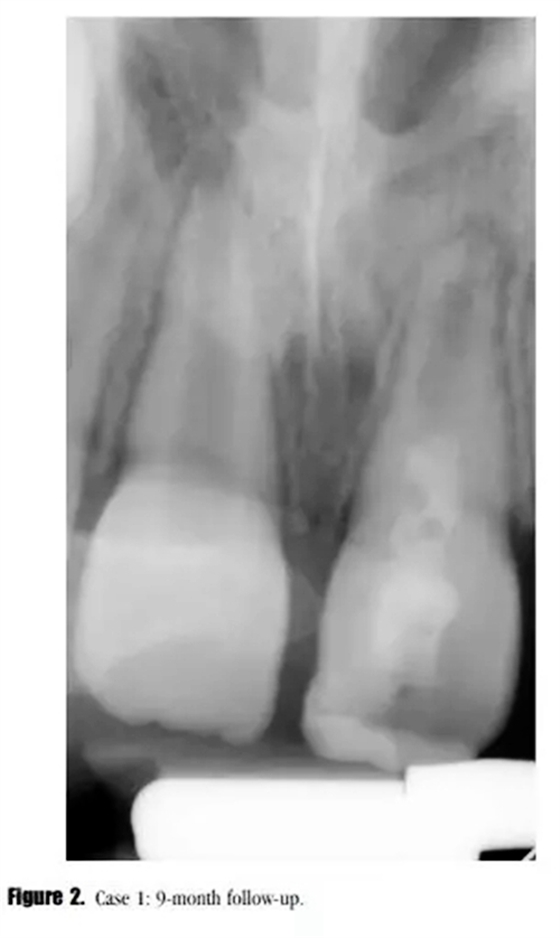

在3,6,9個月的隨后跟蹤隨訪中,患者完全沒有癥狀。與鄰牙和對側牙對比,21的叩診、捫診以及牙周袋深度都在正常范圍內。對于牙髓溫度測試沒有反應。影像學評估顯示,根尖區(qū)低密度透射影像范圍減小,牙根發(fā)育為I型(按照Chueh等人的研究)(圖2),

在第12個月的評估中,叩診與捫診又輕微不適。在臨床牙冠上未發(fā)現(xiàn)充填材料與牙體的縫隙以及隱裂線,探診深度正常。我們采用了一種細菌加強型封閉劑來預防再感染。影像學評估顯示,根尖周投射影增大、牙根停止發(fā)育,以及近中根管內壁的輕微吸收。(圖3)